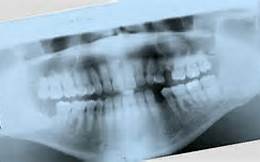

While paper scanning is an office task and can be done with general office equipment, any type of medical film digitizing, including dental film, is an imaging procedure governed by medical and industry regulations. Therefore, dental film digitizing requires specialized equipment that meets the regulations imposed by the FDA. Particular attention must be paid to accurately and reliably scanning the details in medical and dental films because a medical opinion and/or treatment decision will be made about patient care based on these scanned images. When making a diagnosis from an x-ray, image quality is everything.

Make sure that the dental digitizer you choose supports scanning of all dental film sizes: Panoramic, Cephalometric, and Intraoral.

VIDAR offers high-speed digitizing of dental images without sacrificing quality, and supports the digitization of all dental film sizes – for Panoramic, Cephalometric, and Bitewing films (in approved film holders).